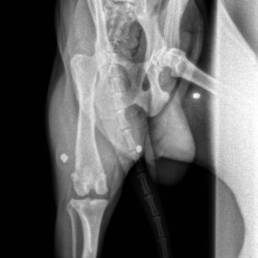

Rocky’s X‑rays told the truth before he could: three buckshot pellets lodged in his hips and hindquarters — and the vet warned there may be more hidden deeper in his body. Someone had shot him, then left him to suffer.

Soon after rescue, Rocky began limping badly on his right hind leg. The veterinary team discovered a torn ACL (Anterior Cruciate Ligament) and mild hip dysplasia on top of the buckshot wounds. During surgery, his torn ligament was repaired, the visible pellets were removed, and he was also neutered to prepare him for a brighter future.